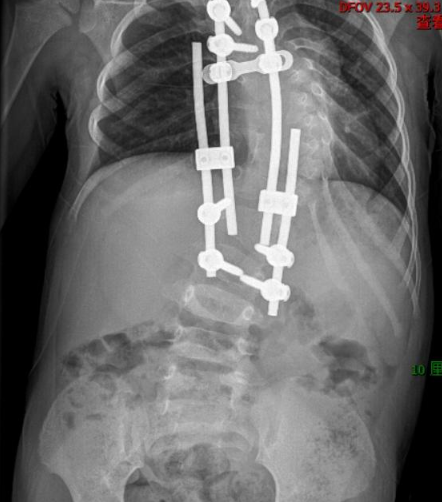

2015 年,2 岁半的可可在武汉儿童医院接受了一期手术,专家在她的胸椎、腰椎植入 4 根生长棒和 8 枚椎弓根钉当「支架」,尽可能给扭曲的脊柱以支撑,延缓侧弯的进展,同时为胸腔和内脏争取生长空间。

此后的 9 年时间,可可每年接受一次调整手术。周治国团队根据生长和矫正情况,对生长棒进行延长和调整,一点点「掰直」扭曲的脊柱。最终,可可脊柱侧弯的度数从 90 度降至 72 度,这也为后期手术争取到机会。